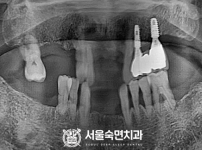

임플란트-전후사진2

치과를-선택할-때-꼭-확인하세요-서울숙면치과-임플란트-전후사진